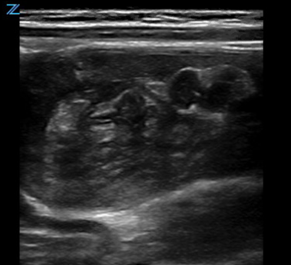

Classically, intussusception manifests in the transverse orientation as a ‘target sign’ or ‘donut sign’ (Figure 1) representing layers of intestine within the intestine. In the longitudinal orientation, the layers of intestine appear as a ‘pitchfork’ or ‘submarine sandwich’ (Figure 2). These findings are most commonly seen in the right lower quadrant for ileocolic intussusception, which is the most common type of intussusception. Small bowel intussusceptions can be differentiated by their size, which are often ≤3 cm.5 While small bowel intussusceptions often spontaneously reduce, if symptoms and findings persist, computed tomography (CT) may be necessary to determine management. POCUS is useful in differentiating variants of intussusception that range from a surgical emergency to a transient source of abdominal pain allowing clinicians to better manage these patients.6

Figure 2. Pitchfork Sign on longitudinal image of intussusception